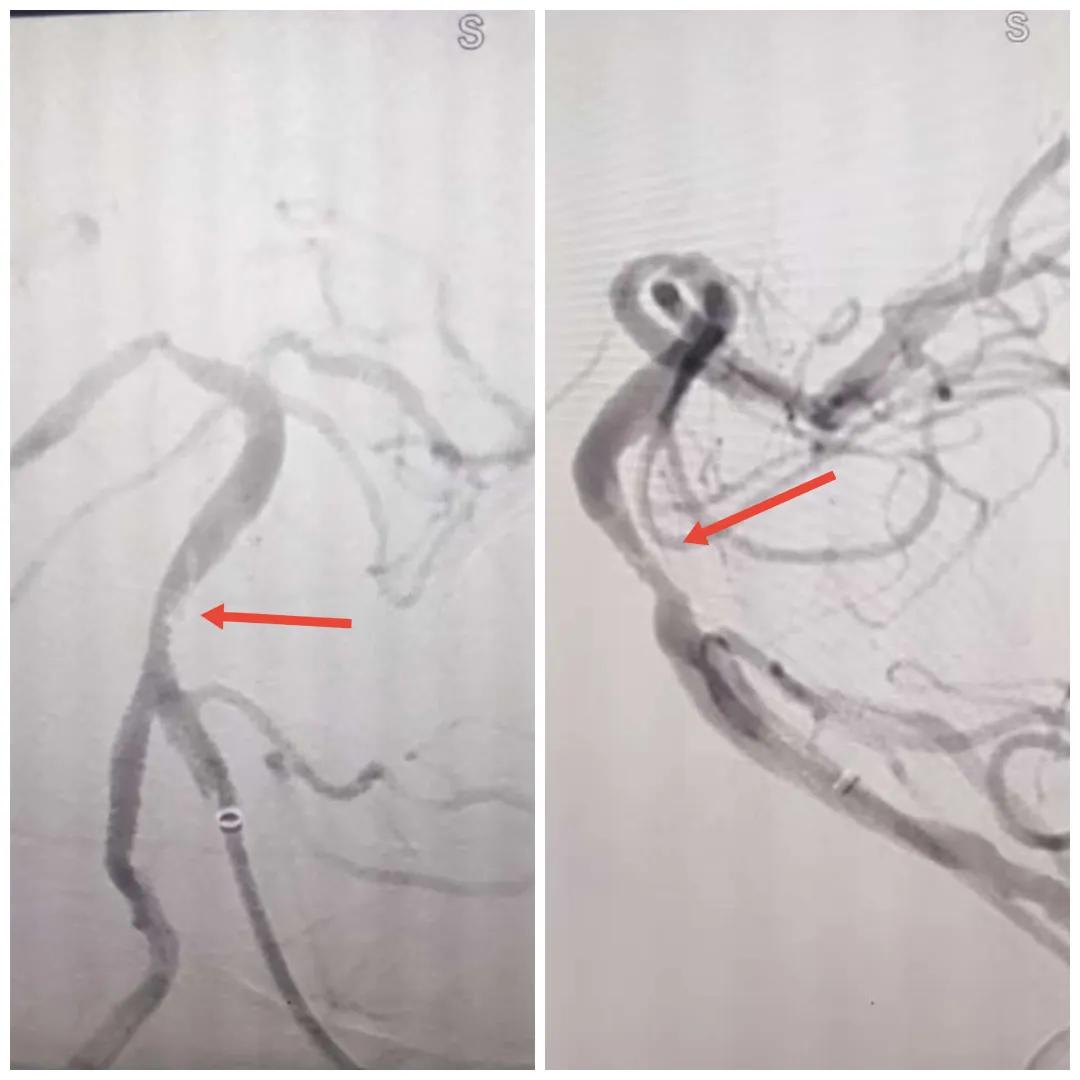

2024年12月19日,漯河市中醫(yī)院腦一科收治了一位79歲的女性患者。患者在入院前2小時(shí)出現(xiàn)言語不利,右側(cè)肢體無力。腦一科醫(yī)師關(guān)卓杰接診后,全面評估患者病情,給予其靜脈溶栓,并急查頭顱MR。影像可見腦干、雙側(cè)枕葉、左側(cè)海馬旁回及丘腦新發(fā)梗塞灶,基底動(dòng)脈閉塞。患者在靜脈溶栓完畢后仍出現(xiàn)陣發(fā)性言語不利、右側(cè)肢體無力、頭暈。立即進(jìn)行科室間會(huì)診,副主任醫(yī)師彭壯考慮患者出現(xiàn)上述癥狀與其基底動(dòng)脈閉塞后顱內(nèi)動(dòng)脈代償不良有較大關(guān)系,且基底動(dòng)脈閉塞有較高的致死率與致殘率,建議行急診取栓,降低患者死亡及殘障風(fēng)險(xiǎn)。家屬了解病情,知情同意后要求行介入治療。

磁共振MRA提示基底動(dòng)脈閉塞

在經(jīng)造影后,主刀醫(yī)生腦一科副主任楊慶堂發(fā)現(xiàn)患者基底動(dòng)脈下段重度狹窄且狹窄段以遠(yuǎn)有大負(fù)荷血栓,其狹窄處考慮為動(dòng)脈夾層,手術(shù)難度及風(fēng)險(xiǎn)較大。楊慶堂副主任在彭壯副主任醫(yī)師的協(xié)助下運(yùn)用spaceman(太空人)技術(shù),中間導(dǎo)管抵近血栓抽吸配合支架拉栓,成功開通血管。再次造影可見基底動(dòng)脈管腔明顯增寬,遠(yuǎn)端血管顯影良好,且等待20分鐘后造影仍顯示血流通暢。楊慶堂副主任考慮到本次手術(shù)時(shí)間不宜過長,現(xiàn)患者基底動(dòng)脈及分支前向血流維持良好,給予其抗栓藥物應(yīng)用后結(jié)束手術(shù),并建議患者3個(gè)月后復(fù)查造影,明確其基底動(dòng)脈夾層情況。

造影可見血管夾層和大量血栓形成

取栓后血管管腔增寬,前向血流良好